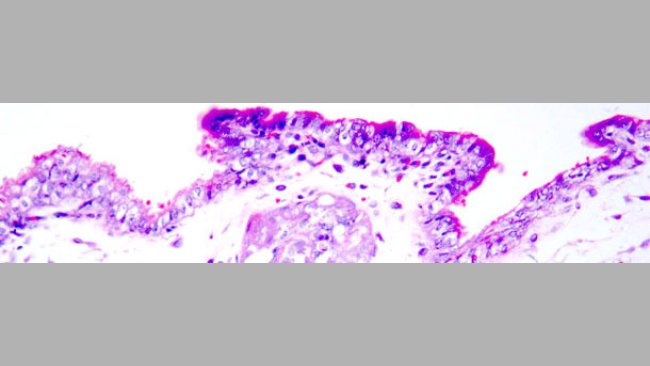

Transmissão placentária do circovirus suíno tipo 2

O PCV2 pode alcançar os embriões/fetos atravessando a placenta durante a virémia ou através da inseminação com sémen contaminado.